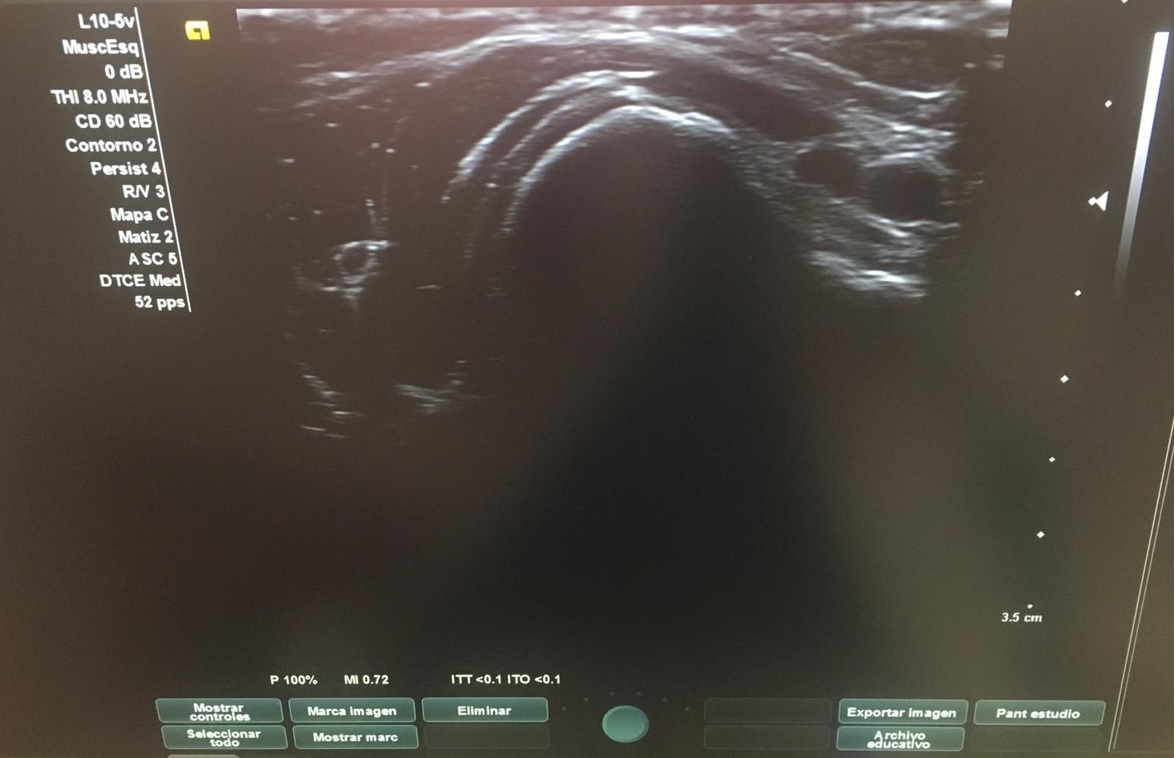

Con el objetivo de no irradiar al escolar, se decide realizar una ecografía desde el centro de salud, para poder obtener una mayor aproximación diagnóstica.

Ecografía: La tumoración referida corresponde a una excrecencia ósea con ribete hipoecoico circunante de 1 mm de espesor, sugestiva de lesión osteocondral.

Tras visualizar alteración en la ecografía del centro de salud, se deriva a radiología para realizar ecografía reglada y completar estudio con radiografía, así como realizar derivación para valoración por parte de Traumatología del Hospital Santa Lucía.